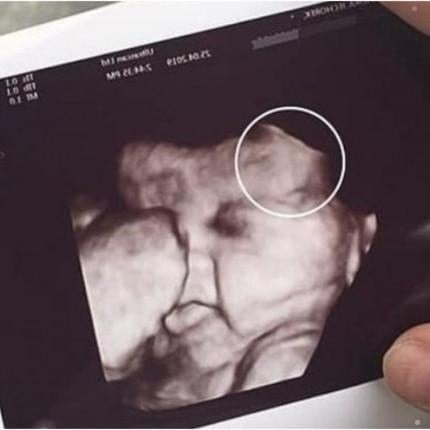

Doctors later explained that the initial scan had displayed an unexpected shape next to the developing baby, prompting the need for additional imaging. After a follow-up exam, they determined it was a benign artifact—a harmless visual distortion caused by the baby’s position and the machine’s angle. The clarification brought immense relief to both women, who had been preparing themselves for difficult news.

The family later expressed gratitude to the clinic for handling the situation with care and transparency. Medical specialists remind expecting parents that unusual ultrasound images are not uncommon and often resolve with clearer scans. The incident underscores the emotional weight of prenatal appointments and the importance of compassionate communication in moments of uncertainty.